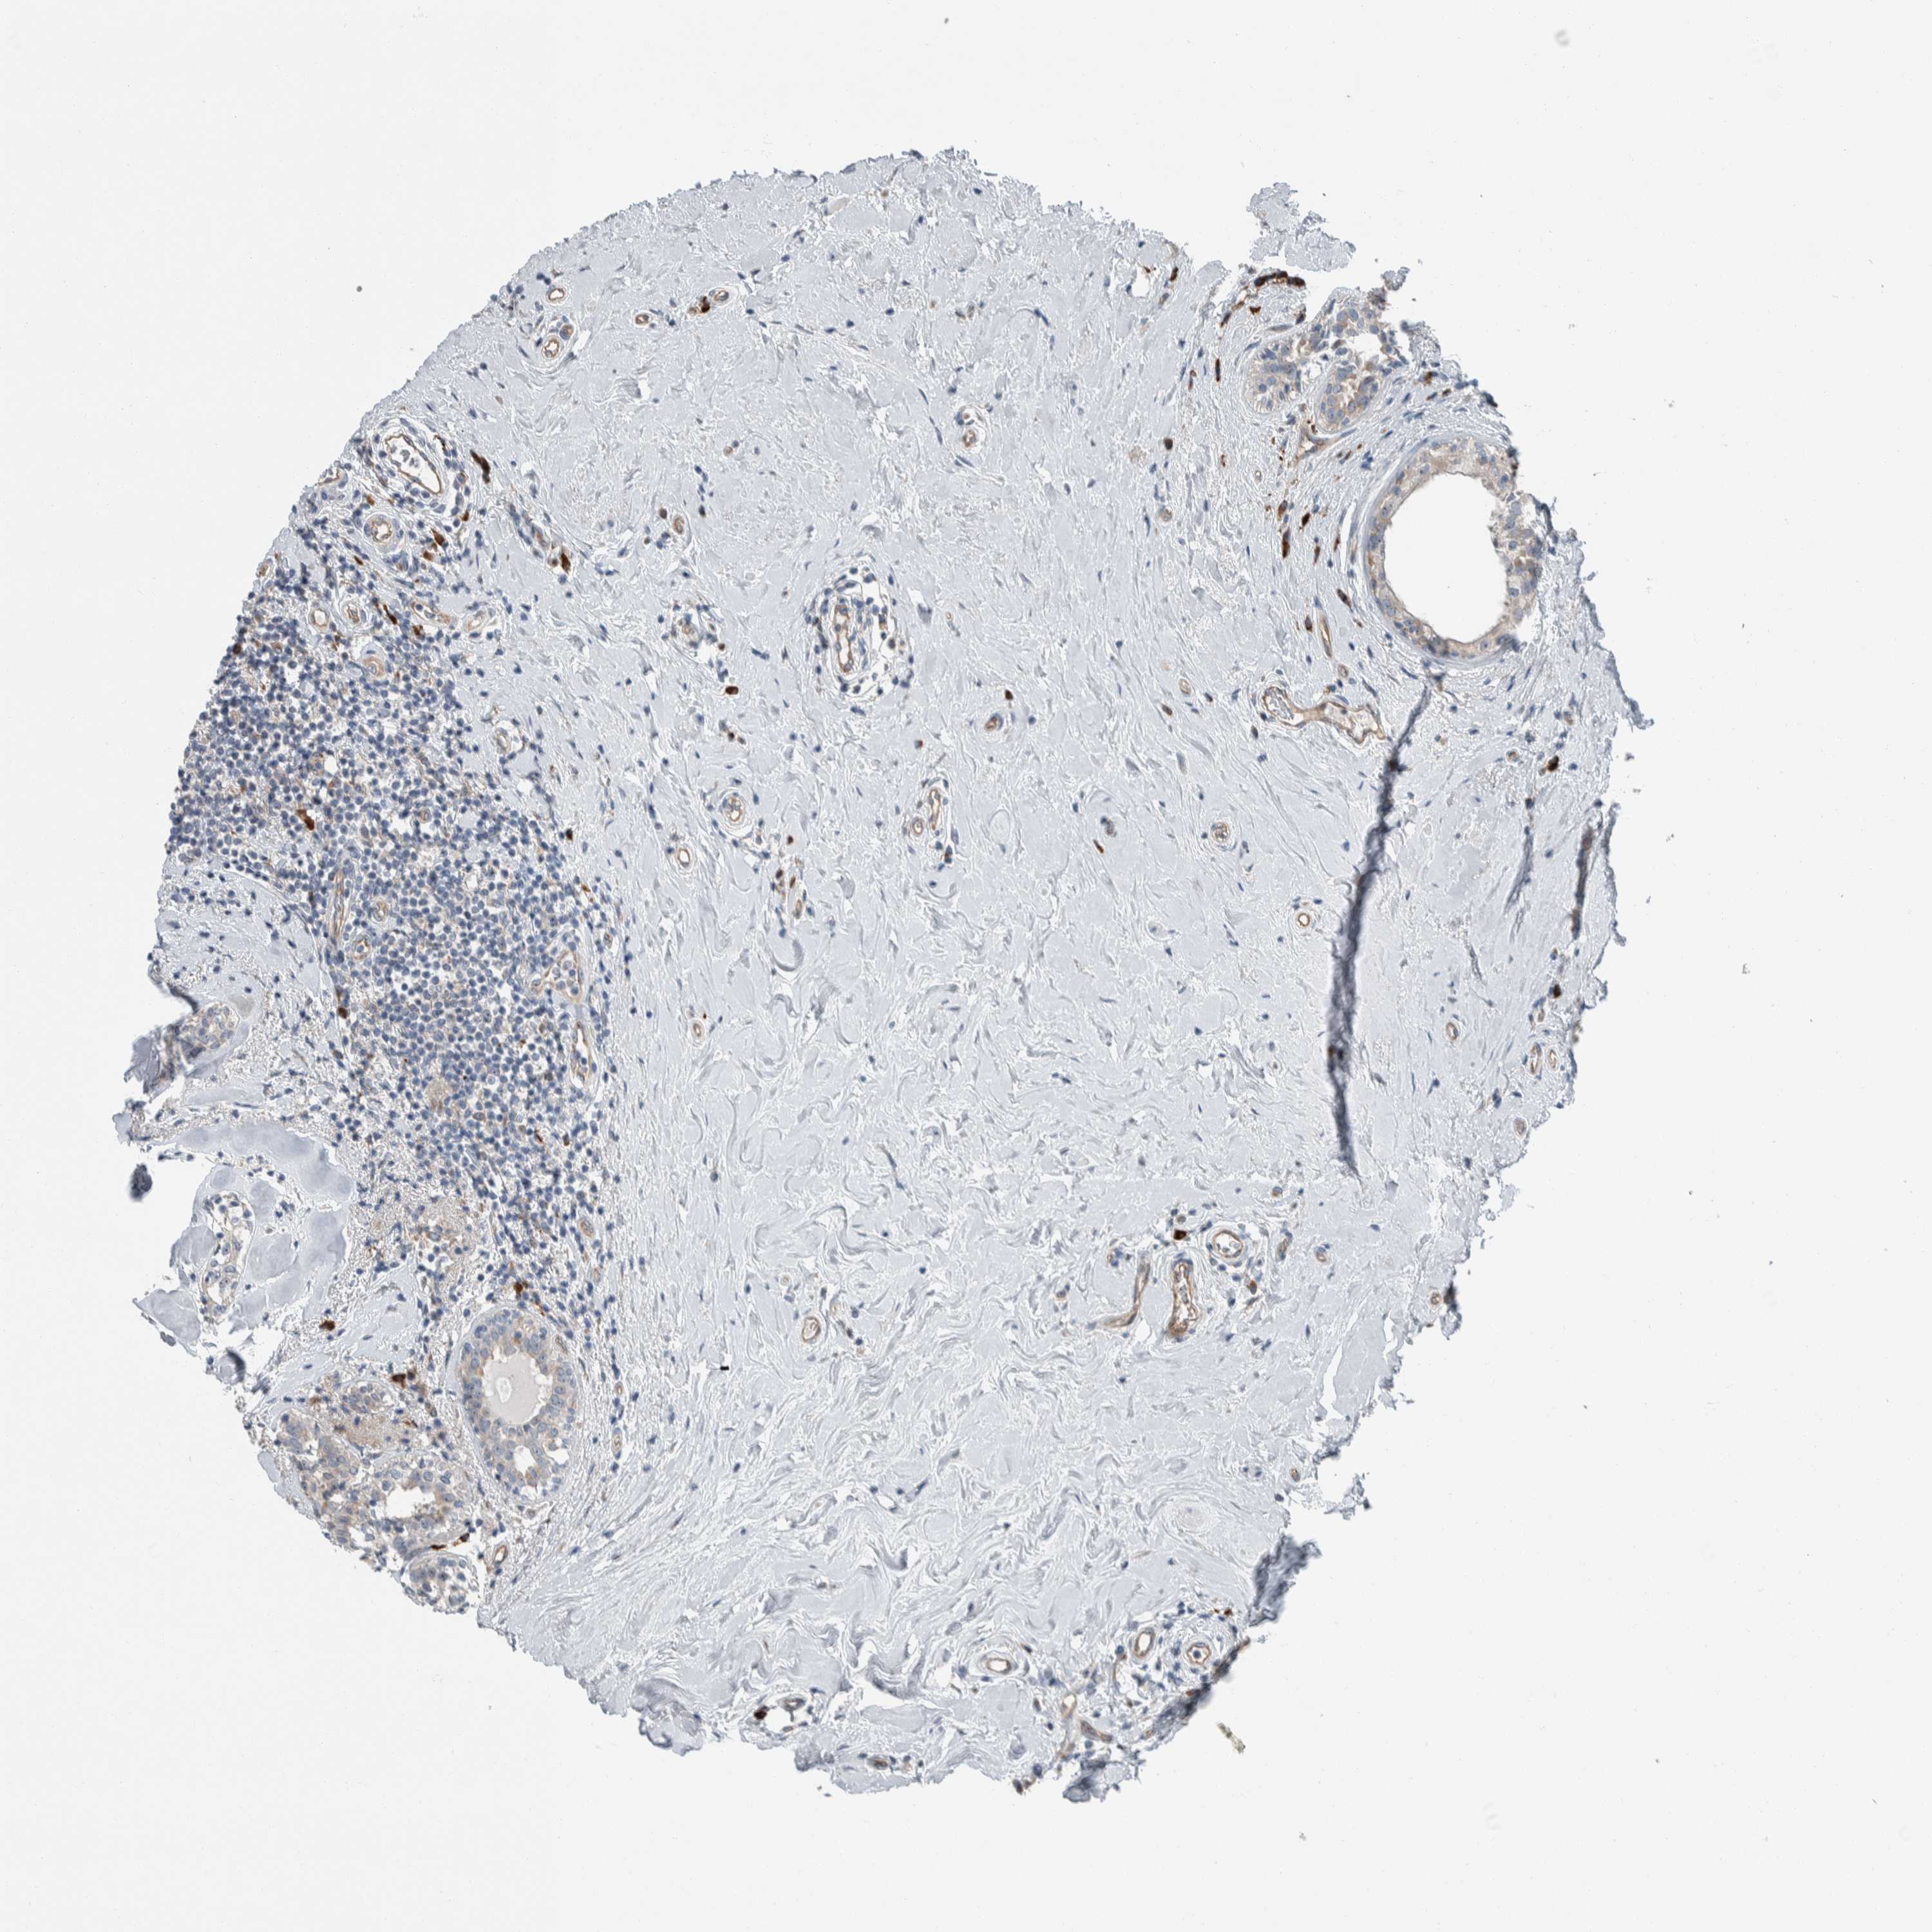

CANCER BREAST CANCER Show tissue menu

BRCA TCGA BRCA VALIDATION PROTEIN EXPRESSION